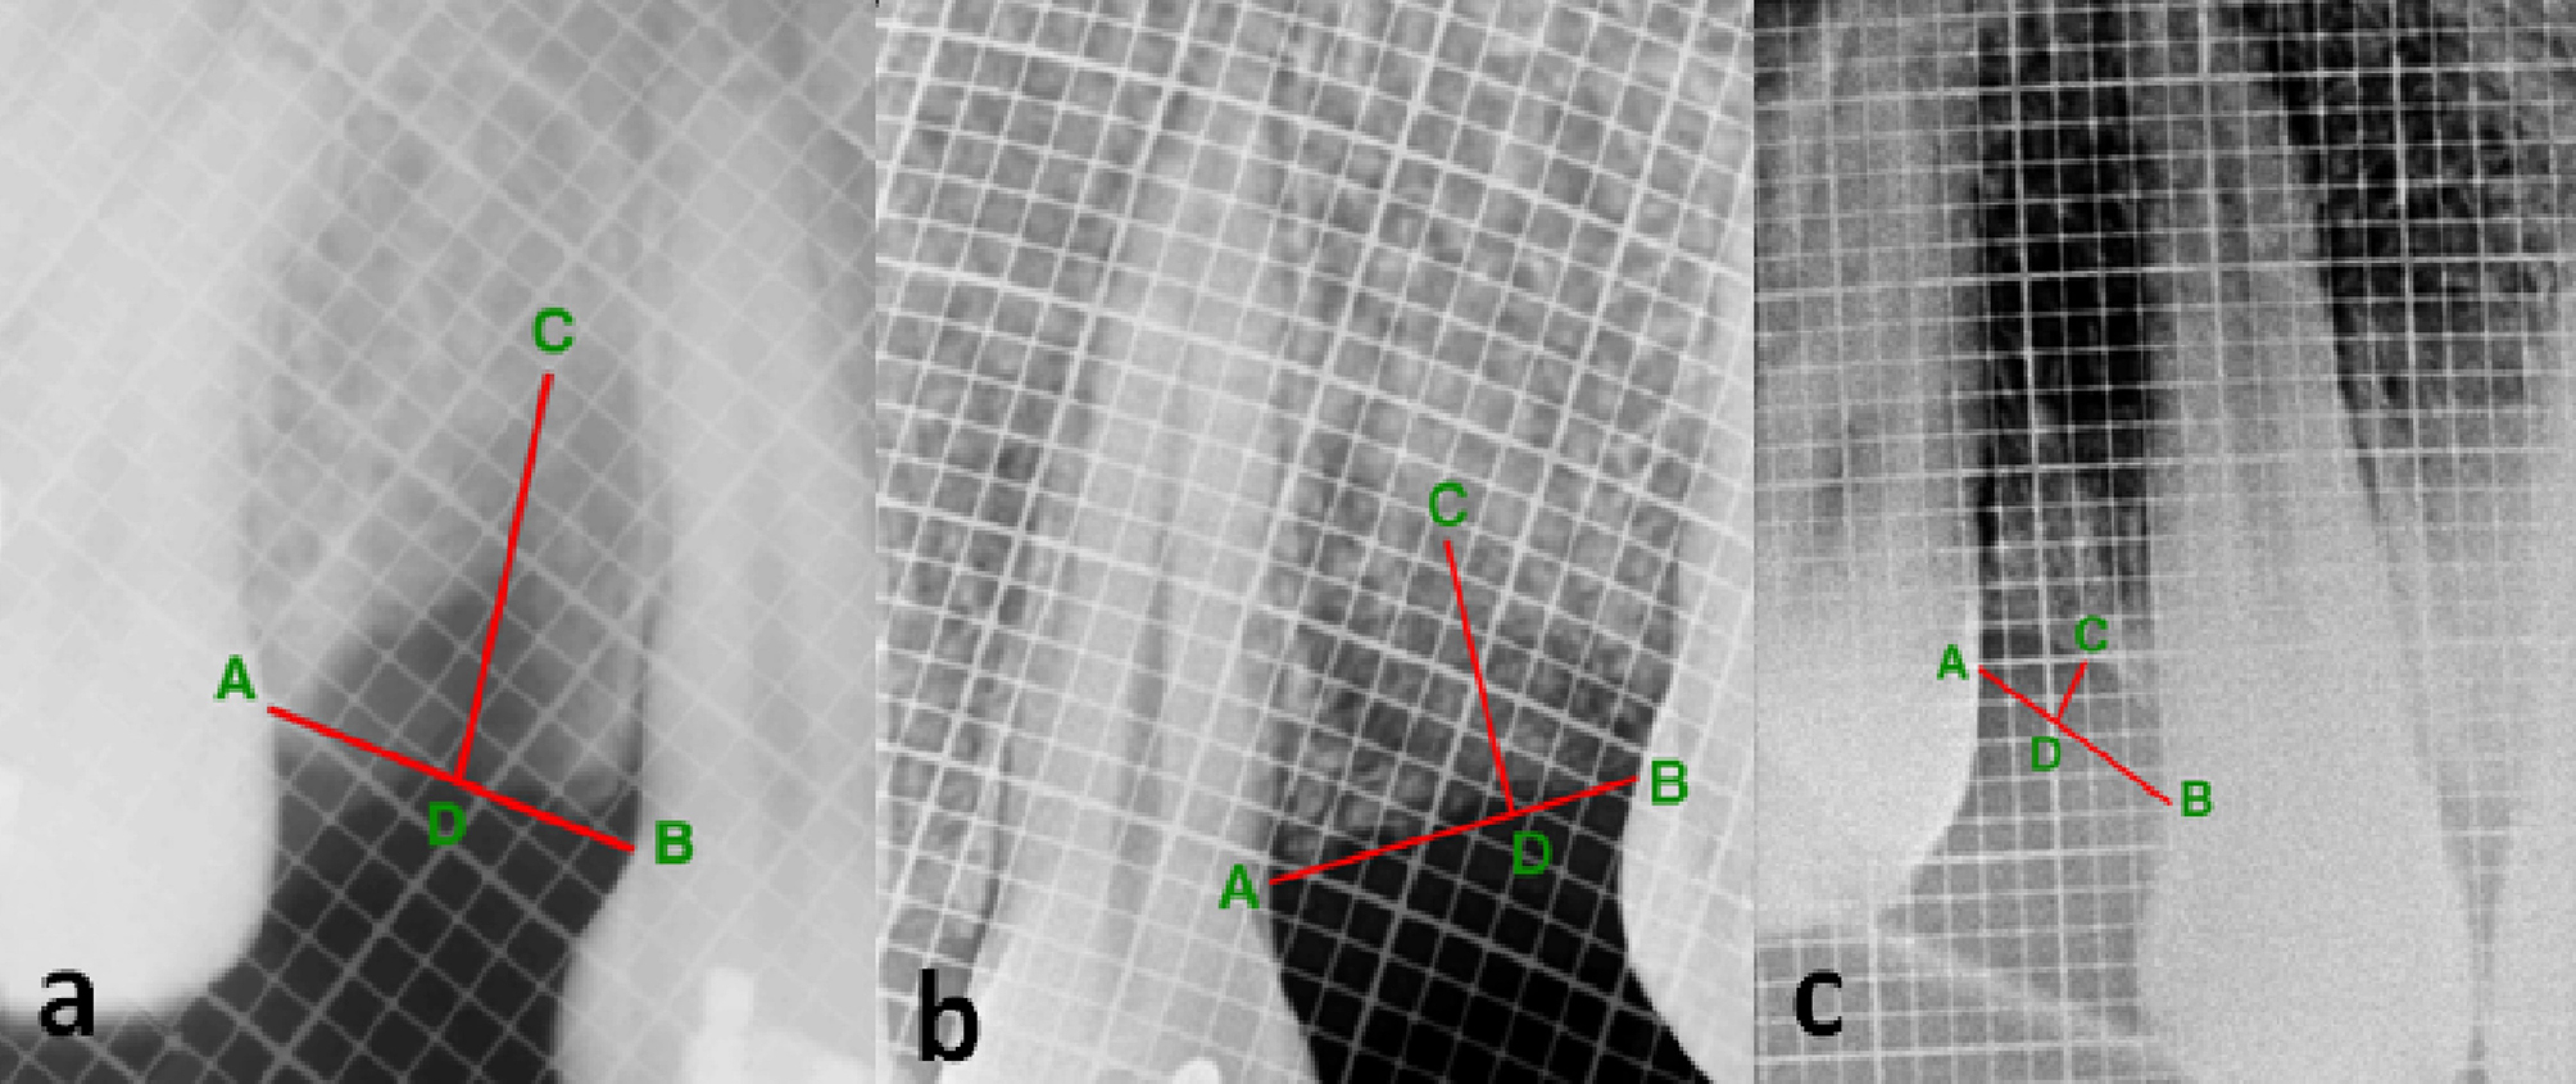

The height of the alveolar bone was assessed by the radiovisiography (RVG) (Carestream Health Inc., NY, USA) technique. A connecting line (AB) was drawn from the cementoenamel junctions (CEJ) of adjacent teeth on the mesial and distal aspects of the extraction socket. The lowest position on the alveolar ridge defect was marked as point C. A line was drawn from C, keeping it perpendicular to the line AB. Point D was marked on line AB, at the intersection of the line drawn from C. The distance of CD was measured at 3- and 6-month follow-up visits. A radiopaque millimeter-graduated grid (Bluedent India Private Ltd., Chennai) was used to standardize the assessment of the height of the alveolar bone radiographically across the extraction socket postoperatively. A decrease in the length of CD signified an increase in bone height and vice-versa (Figure 1).

Postoperative radiograph of the grafted site at (a) baseline, (b) 3 months, and (c) 6 months, showing the measurement of alveolar bone height.